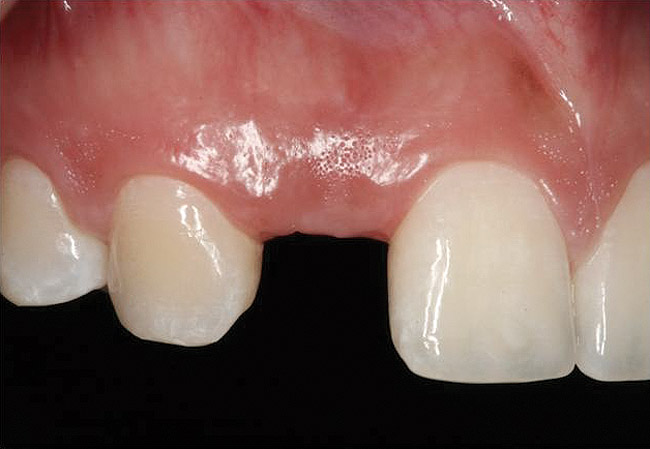

Figure 4  Characterization of the interproximal bone and tooth contacts: A periapical radiograph assists in measuring the distance from bone crest to the adjacent tooth contact points for missing tooth No. 8. The mesial bone crest to the adjacent tooth contact distance is < 5 mm, while the distal bone crest to adjacent tooth contact distance is > 6 mm (Fig 4). One-year following implant placement, conservation of these dimensions is revealed (Fig 5). The clinical photograph (Fig 6) of the lateral incisor adjacent to tooth No. 8 implant crown demonstrates that the absence of distal interproximal (papilla) fill related to the observed bone crest to contact distance exceeds 6 mm.

Figure 5  Characterization of the interproximal bone and tooth contacts: A periapical radiograph assists in measuring the distance from bone crest to the adjacent tooth contact points for missing tooth No. 8. The mesial bone crest to the adjacent tooth contact distance is < 5 mm, while the distal bone crest to adjacent tooth contact distance is > 6 mm (Fig 4). One-year following implant placement, conservation of these dimensions is revealed (Fig 5). The clinical photograph (Fig 6) of the lateral incisor adjacent to tooth No. 8 implant crown demonstrates that the absence of distal interproximal (papilla) fill related to the observed bone crest to contact distance exceeds 6 mm.

Figure 6  Characterization of the interproximal bone and tooth contacts: A periapical radiograph assists in measuring the distance from bone crest to the adjacent tooth contact points for missing tooth No. 8. The mesial bone crest to the adjacent tooth contact distance is < 5 mm, while the distal bone crest to adjacent tooth contact distance is > 6 mm (Fig 4). One-year following implant placement, conservation of these dimensions is revealed (Fig 5). The clinical photograph (Fig 6) of the lateral incisor adjacent to tooth No. 8 implant crown demonstrates that the absence of distal interproximal (papilla) fill related to the observed bone crest to contact distance exceeds 6 mm.

Additional attention must be paid to the osseous architecture related to the adjacent teeth, as this controls interproximal tissue form.7 The crest of healthy bone is 4.5 mm to 5 mm from the contact point between anterior teeth8; a similar 5-mm distance from the contact point to the bone crest has been measured between an implant and natural tooth. An important and additional rule to guide esthetic implant outcomes is that the adjacent tooth should possess interproximal bone levels no further than 6 mm from the natural tooth contact point (Figure 4 through Figure 6). While the ideal distance is justifiably indicated to be 5 mm, this 6-mm rule establishes a point at which marked interproximal tissue deficiencies and asymmetry will not be overcome.